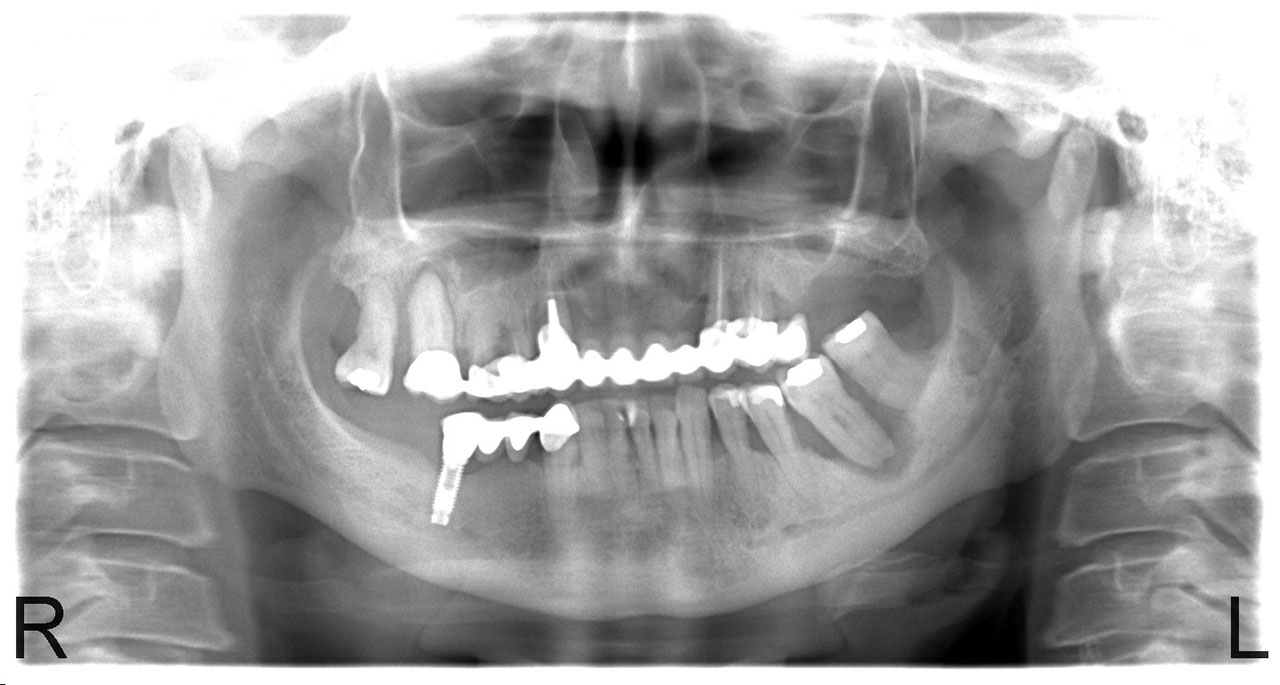

• esettanulmany-01

Implantáció előtt, gyulladt, törött fogak.